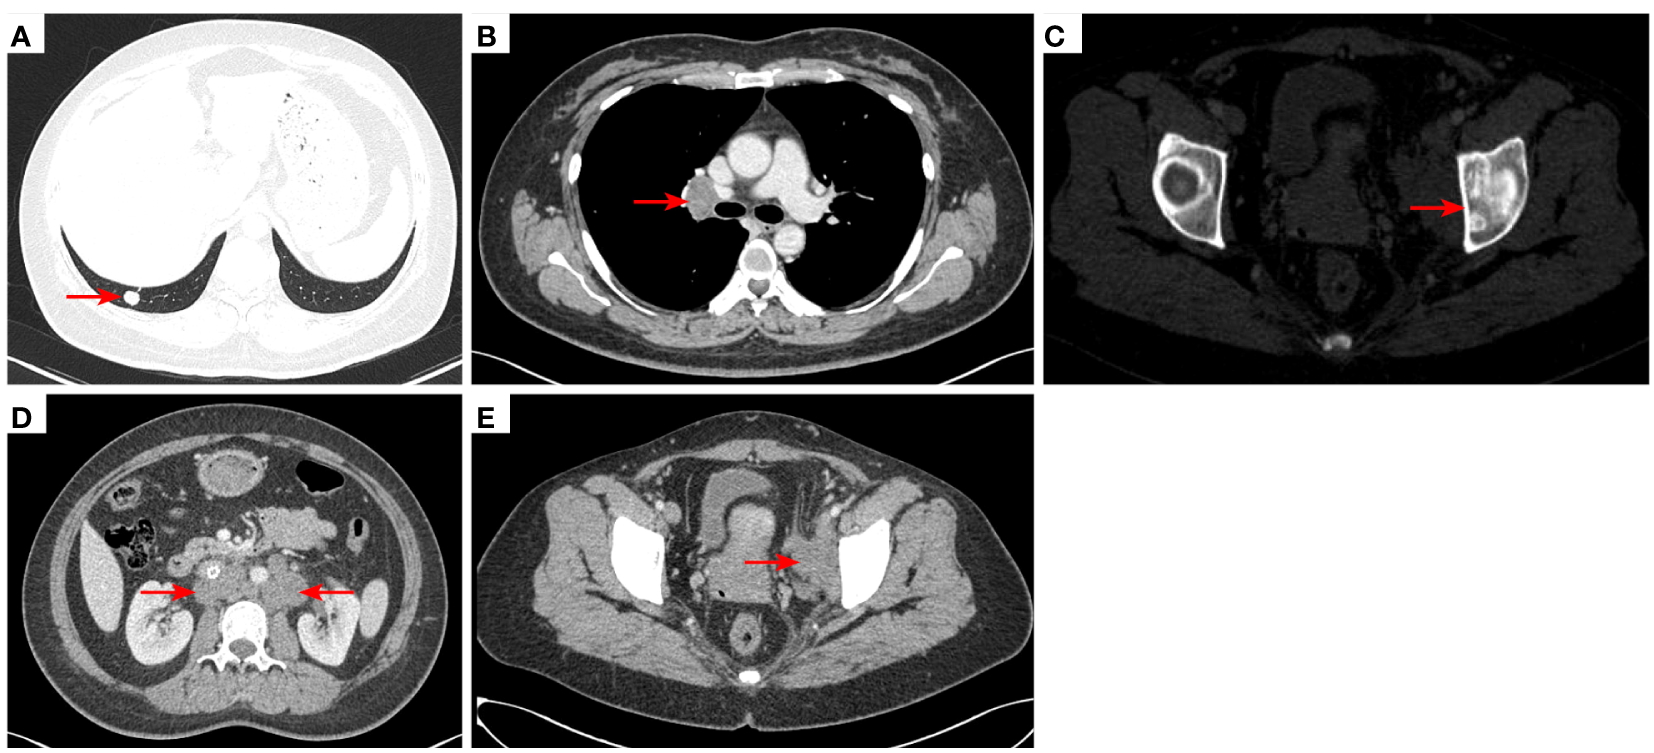

Figure 4

2020–11-3 CT scan: The original right lower lobe of the lung metastatic tumor disappeared (A); short diameter of new right hilar lymph node was 0.83 cm [red arrow, (B)]; Left acetabular metastases (red arrow, (C)). The short diameter of retroperitoneal lymph nodes was 1.01 cm which was bigger than before [red arrow, (D)], and the short diameter of left pelvic lymph nodes was 2.76 cm [red arrow, (E)]. The efficacy was PD. PD, progressive disease.